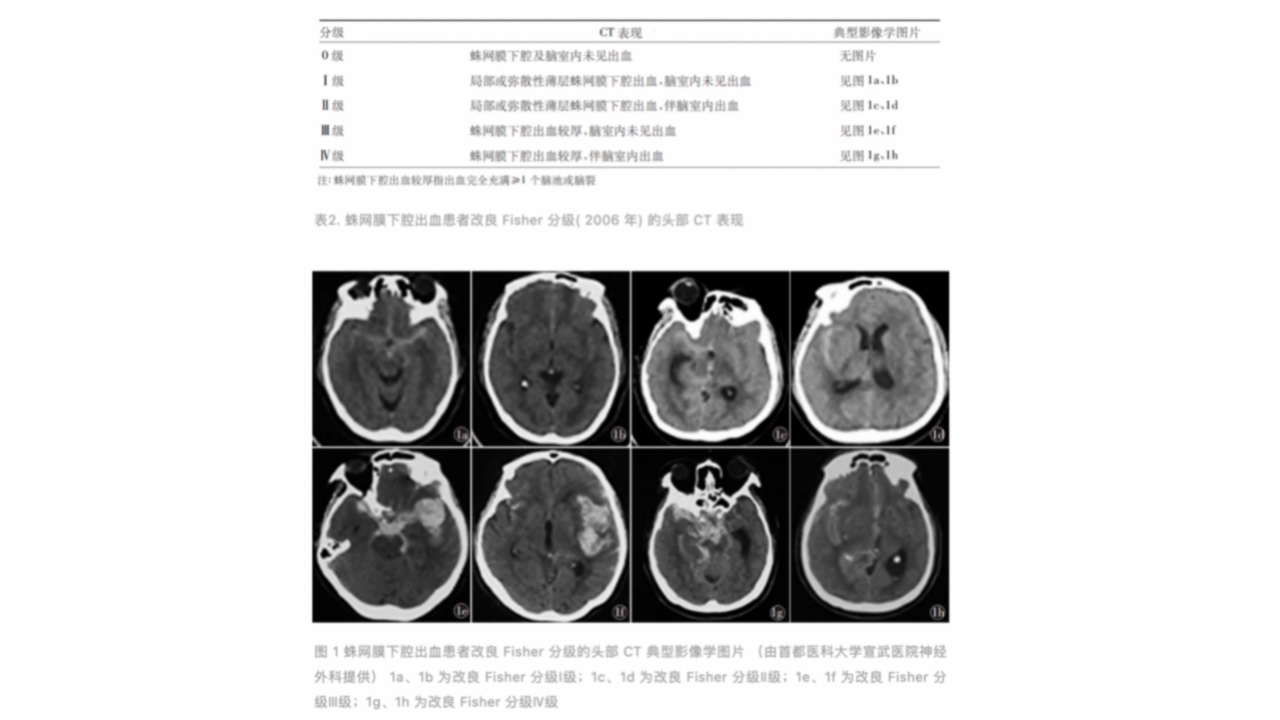

蛛网膜下腔出血患者改良Fisher分级(2006年)的头部CT表现见表3[22],其典型影像学图片见图1。